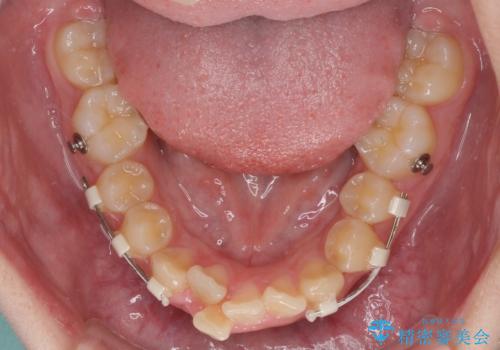

インビザライン単体で対応ることも検討できますが、達成する可能性が低いため、カリエールディスタライザーという補助装置を併用して、より確実性を上げることとしました。

奥歯の咬み合わせと深い咬み合わせを改善した後、インビザラインで歯列を整えることとしました。

ワイヤー装置と補助装置を有効に活用し、さらには高校生ということもあり、1年9か月で狙い通りの仕上がりを達成することができました。